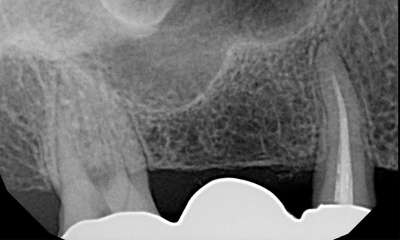

Fractured tooth fixed with a tooth colored composite filling.